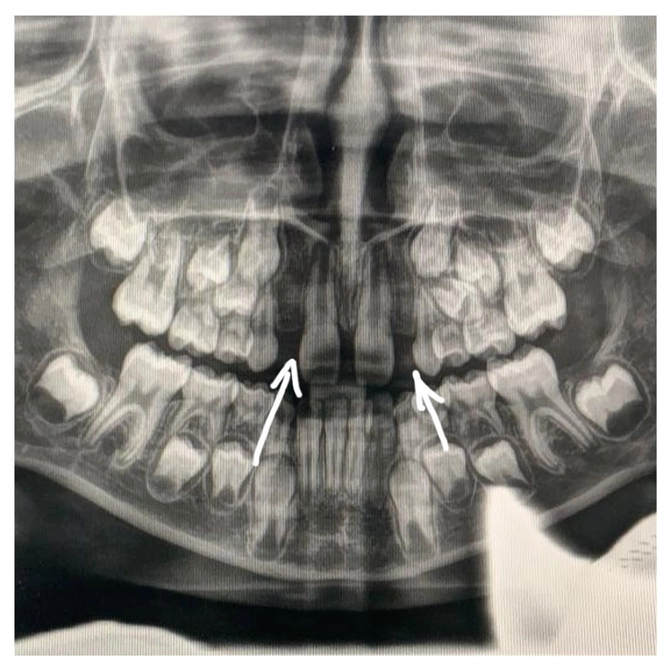

А произошло вот что: молочные боковые резцы на верхней челюсти выпали, а постоянные никак не растут.

К слову, до этого девочке ни разу не делали общий панорамный снимок всех челюстей (ОПТГ).

Поэтому и не знали, что зачатков постоянных резцов нет и ждать их появления бессмысленно.